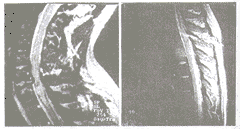

MRI對軟組織的良好解析度使其在脊髓損傷中使用廣泛;同樣,在樞椎椎體骨折患者中,MRI可清楚顯示脊髓損傷和受壓的情況。